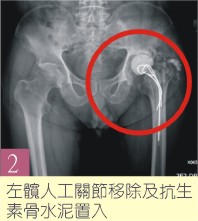

骨科范姜治澐醫師表示,林先生求診時關節疼痛且傷口已有滲液產生,故強烈懷疑已有人工關節感染之情形,經X光檢查發現左髖人工關節並無明顯鬆脫,抽血報告發現發炎指數及白血球都有升高之情形,於是第一階段安排了左髖人工關節移除、清創,及抗生素骨水泥置入手術,術後根據術中細菌培養的結果投予靜脈抗生素治療兩周後,傷口恢復良好並順利出院。